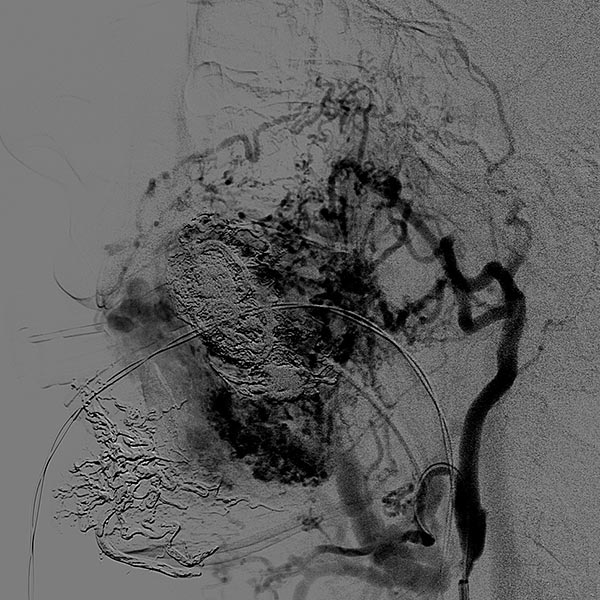

Axiale, T2-gewichtete MRT auf Höhe der Wange zeigt die AVM relativ hyperintens mit Ödem des Gewebes und Ausdehnung bis zum linken Unterkiefer. Im rostralen Abschnitt auch einige schwarze flow-voids durch stark durchblutete Arterien innerhalb der AVM.

Die koronare, fettunterdrückte T1-gewichtete MRT nach Kontrastmittelgabe zeigt das inhomogene deutliche Enhancement der AVM, das typisch ist für eine AVM im Stadium der Proliferation (entsprechend der schnellen klinischen Vergrößerung) und gut mit dem Ödem in den T2-gewichteten Aufnahmen korreliert.

Koronare, T2-gewichtete, fettgesättigte MRT mit Ödem innerhalb der AVM sowie gut sichtbaren flow-voids durch die enthaltenen Arterien mit hohem Durchfluss.

Inhomogenes, vor allem peripheres Enhancement der proliferierenden AVM in dieser axialen fettunterdrückten T1-gewichteten MRT nach Kontrastmittelgabe. Keine abgrenzbare, eigentlich solide Komponente, anders als bei einem echten vaskulären Tumor.